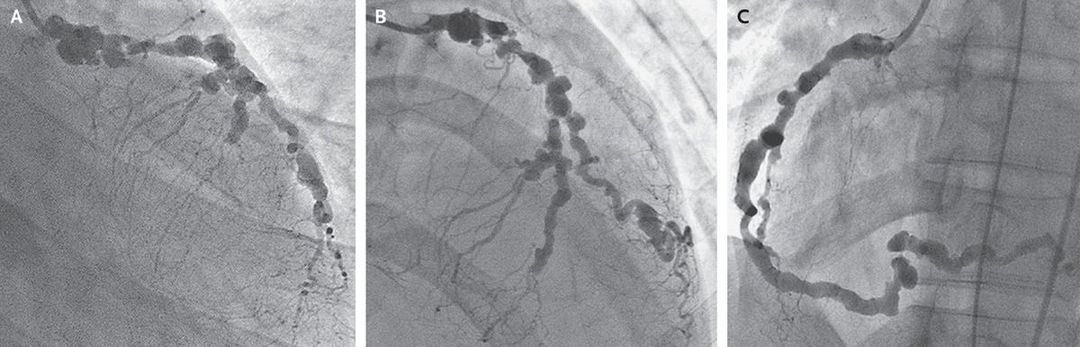

A 25-year-old woman who had just undergone cardiac arrest due to ventricular fibrillation was brought to the hospital and admitted and was thereafter successfully resuscitated and cooled. Initially, no additional history could be obtained. Serial electrocardiography revealed marked anterolateral ST-segment depressions. Findings on coronary angiography were consistent with severe generalized coronary arteritis (Panels A, B, and C). Her coronary disease was deemed unamenable to intervention. Her history revealed that she had been given a diagnosis of polyarteritis nodosa 3 years earlier and was receiving prednisolone maintenance therapy. Previous angiography had shown extensive coronary artery involvement but only minor left ventricular dysfunction. The current images showed significant progression of angiographic disease, including new critical stenoses of the proximal left anterior descending artery and the posterior left ventricular branch. Although severe cardiac involvement in polyarteritis nodosa is unusual, it can result in myocardial infarction and confers a poorer prognosis. Soon after the patient was treated at the hospital, recurrent pulmonary edema developed as a result of severe mitral regurgitation and left ventricular dysfunction. Given the extensive extracardiac disease, she was not a candidate for cardiac transplantation. Azathioprine was added to her treatment with prednisolone, but the patient died within several months.